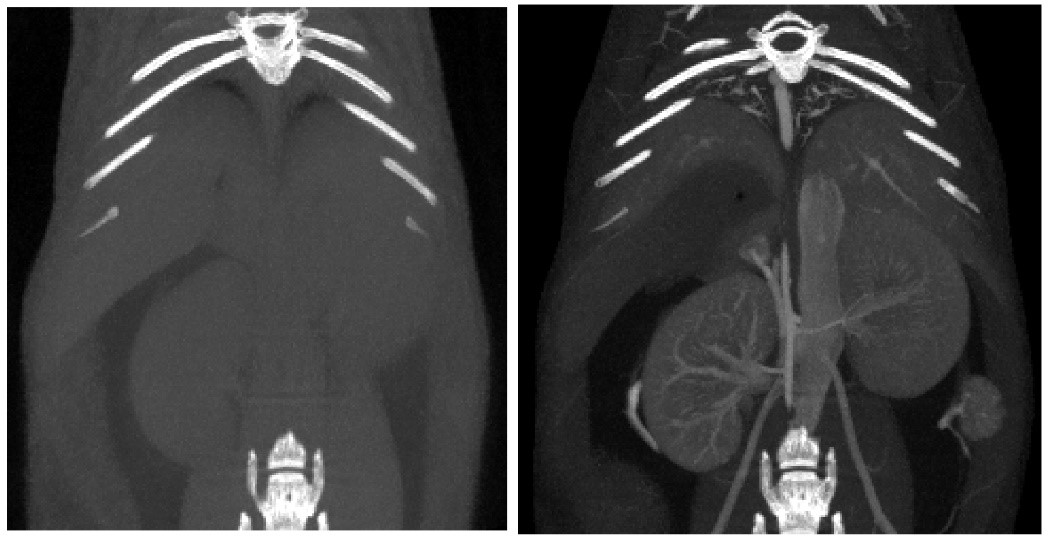

對比增強CT.jpg